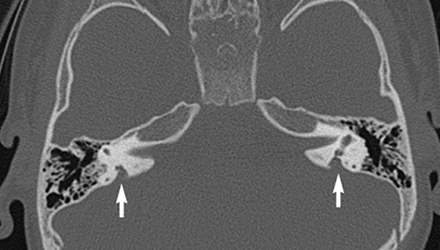

SLC26A4基因定位于人類染色體7q31,SLC26A4基因和大前庭導(dǎo)水管綜合征相關(guān)突變位點(diǎn)的發(fā)現(xiàn),證實(shí)SLC26A4是大前庭導(dǎo)水管綜合征的責(zé)任基因。

我們平時(shí)提到的“一巴掌打聾”、“一跤摔聾”其實(shí)都與SLC26A4基因突變有關(guān),絕大多數(shù)大前庭導(dǎo)水管綜合征都是SLC26A4基因突變?nèi)堑牡湣?/p>

SLC26A4基因編碼一種叫“Pendrin”的跨膜轉(zhuǎn)運(yùn)蛋白,在機(jī)體離子成分平衡的維持中發(fā)揮重要作用。

在內(nèi)耳,Pendrin表達(dá)于內(nèi)淋巴管、內(nèi)淋巴囊、橢圓囊、球囊等處,異變的蛋白將對(duì)這些結(jié)構(gòu)的正常生理功能產(chǎn)生影響,引發(fā)聽損。

聽力損失表現(xiàn):

SLC26A4基因突變導(dǎo)致的大前庭導(dǎo)水管綜合征的典型表現(xiàn)為兒童時(shí)期的聽力損失,90%的患者為雙側(cè)性,聽力損失程度不一,可表現(xiàn)為接近正常或重-極重度。

病程可為穩(wěn)定性、進(jìn)行性或波動(dòng)性,聽力可逐步下降至全聾;跌倒、撞擊等行為或無外界影響都可能引發(fā)聽力的下降。